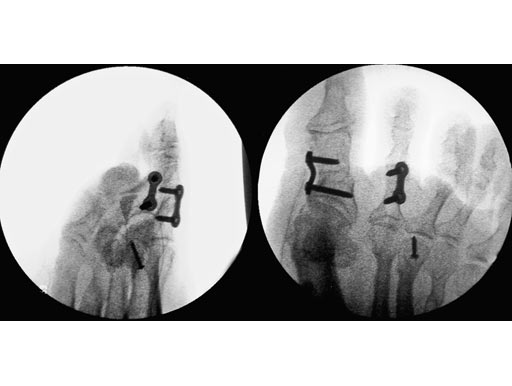

Correction of malunited Akin osteotomy D1 and shortening of the middle phalanx D2 of a flexible hammer toe using a Locking Two-Hole Plate for each correction.